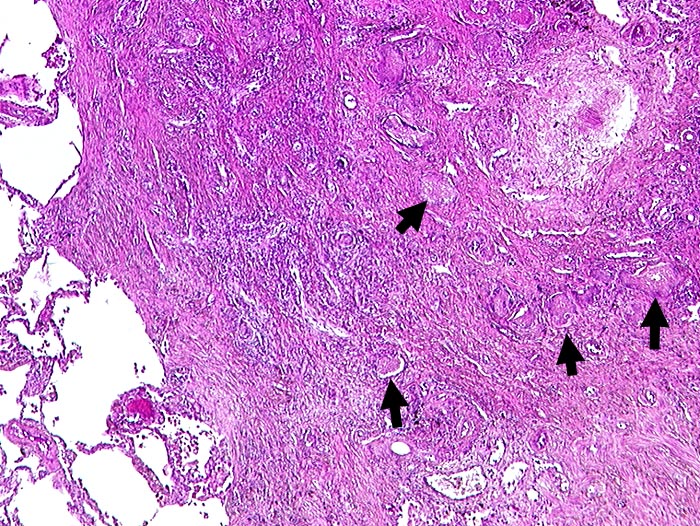

PathoPic ID 269 - Chronische Pneumocystis jirovecii Pneumonie

Chronische Pneumocystis jirovecii Pneumonie

Narbengewebe mit

►

schaumigen Einschlüssen.

In den schaumigen Einschlüssen finden sich bei stärkerer Vergrösserung in der Grocottfärbung zahlreiche Erreger.

AIDS. HIV Positivität bekannt seit 2 Jahren bei iv Drogenabusus.